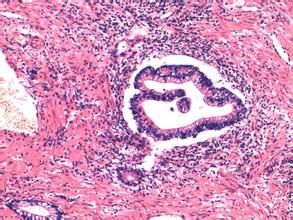

直腸絨毛狀腺瘤癌變 乳頭狀腺瘤絕大多數呈廣基型生長,無長蒂型息肉,瘤體稍高出於正常黏膜面,向周邊蔓延面積較大,典型病例可累及腸管周徑的大部分。瘤表面呈絲絨或粗顆粒或粗毛形狀,顏色較一般息肉狀腺瘤略淡,常復蓋一層粘液。瘤體結構質地較軟,用鉗子輕觸似海棉狀。呈塊狀並有蒂的乳頭狀腺瘤發生極少。病理觀察其瘤的特點是多數纖細的乳頭狀分支,中心為血管結締組織,表面呈單層柱狀或復層上皮及杯狀細胞,腺體成分的結構較少,可有散在分化較差區,病變主要限於黏膜層。很少多發,可並存息肉狀腺瘤。

腸巨大絨毛狀腺瘤 臨床診斷中大多數乳頭狀腺瘤經直腸指檢、直腸鏡或結腸鏡檢發現。由於腺瘤很軟,而直腸指診時腺瘤很軟,需仔細檢查,否則容易被忽略。發現乳頭狀腺瘤要進行仔細捫診全腺瘤,質地均勻而很軟的,屬良性結構的可能性較大。捫及乳頭狀腺瘤有小結節及質硬者須高度警惕癌變的可能。捫診檢查乳頭狀腺瘤有否癌變的早期診斷有一定的可行性。捫診不十分清楚的乳頭狀腺瘤可經直腸鏡、乙狀結腸鏡及結腸纖維內鏡檢診。為確定腫瘤有無癌變可能,須在腺瘤表面及基底不同部位採取組織做活檢。